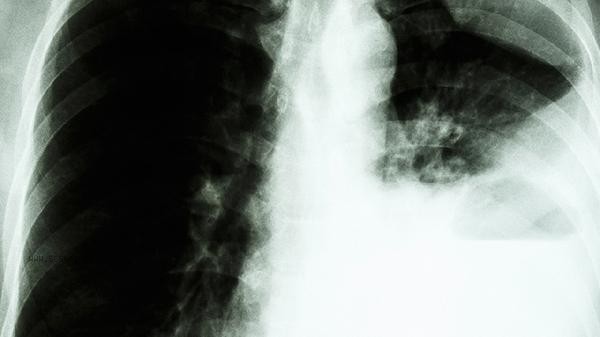

Alveolar ventilation=tidal volume dead space volume x respiratory rate. Adult resting state is about 4-6 liters per minute, which can increase to 100 liters per minute during exercise. The calculation formula involves the correction of approximately 150ml of anatomical dead space and physiological dead space, which requires professional equipment for measurement. Regular lung function testing can help detect respiratory diseases such as chronic obstructive pulmonary disease and asthma early. It is recommended that smokers and dust exposed individuals undergo annual check ups, and daily aerobic exercise such as swimming and jogging can improve lung capacity. Before testing, it is necessary to avoid vigorous exercise and overeating, and wear loose clothing in conjunction with breathing training. When measuring children and adolescents, age correction formulas should be used, and elderly people should pay attention to the impact of osteoporosis on chest range of motion. Individuals with abnormal lung function should undergo further examinations such as chest CT and blood gas analysis.